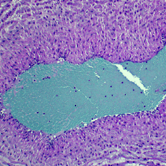

Η ιδέα για τη δημιουργία της εταιρείας Little Cord Art γεννήθηκε όταν οι ιδρυτές της, ο Κιθ και η Στέφανι, περίμεναν το πρώτο τους παιδί το 2009. Σε μια τυπική υπερηχογραφική εξέταση, φάνηκε ότι ο ομφάλιος λώρος είχε δύο αντί για τρία αγγεία –κάτι που συμβαίνει περίπου στο 10% των κυήσεων. Καθώς ο Κιθ είναι γιατρός, θέλησε μετά τη γέννα να ρίξει μια ματιά την ιστολογική εξέταση του λώρου. Και διαπίστωσε ότι η εικόνα που παρουσίαζε ήταν πολύ όμορφη!

Έτσι, αποφάσισαν να φτιάξουν από την εικόνα αυτή ένα πίνακα, τον οποίο κρέμασαν στον τοίχο του παιδικού δωματίου και εντυπωσίαζε όποιον τον έβλεπε όχι μόνο με την ομορφιά αλλά και με την ιστορία του.

Με τη βοήθεια μικροσκοπίου, η εικόνα των κυττάρων του λώρου θα μεγεθυνθεί 400 φορές.

Η εικόνα αυτή θα αποτυπωθεί με τη βοήθεια ψηφιακής κάμερας και θα αποτελέσει την πρώτη ύλη για τη δημιουργία του πίνακα.

Το τελικό στάδιο αφορά το καλλιτεχνικό κομμάτι, καθώς, εστιάζοντας ή απομονώνοντας κομμάτια της εικόνας και δίνοντας την επιθυμητή αντίθεση των χρωμάτων, δημιουργείται ο τελικός πίνακας.